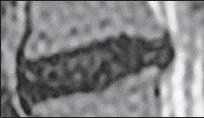

Рисунок № 15. Образное сравнение позвонка и перстня

Не случайно я сравнил тело позвонка с драгоценным камнем. Это действительно драгоценный по функциям элемент позвонка. Дело в том, что тело позвонка состоит из губчатого вещества пористой структуры, которое образовано отдельными костными перекладинами — трабекулами (лат. trabecula — небольшая балка, перекладина), основой микроскопичного строения которых являются костные пластинки. Ячейки губчатого вещества тела позвонка заполнены красным костным мозгом. А красный костный мозг, как известно, это важнейший орган кроветворения и костеобразования, поскольку в его тканях находятся кроветворные элементы (стволовые клетки), клетки, разрушающие кость (остеокласты) и клетки, образующие кость (остеобласты). Ценность заключается в том, что именно от тела позвонка поступает регулярное и единственное питание для межпозвонкового диска через замыкательную (гиалиновую) пластинку, отделяющую губчатую кость тела позвонка от межпозвонкового диска.

О питании межпозвонкового диска мы будем говорить ещё не раз, поскольку это является существенным моментом в понимании причин возникновения и развития многих заболеваний позвоночника. А пока хочу привести наиболее доходчивое сравнение. Жизненно важное питание, поступающее от тела позвонка, представляет собой для межпозвонкового диска практически то же, что, к примеру, в Великую Отечественную войну представляла собой «Дорога жизни» для жителей блокадного Ленинграда (ныне Санкт-Петербурга). Ладожское озеро было тогда, подобно замыкательной пластинке, единственной транспортной магистралью, через которую поступало продовольствие для города. Поскольку мы уж коснулись темы Великой Отечественной войны, то приведу и другое, на сей раз весьма печальное сопоставление. Общеизвестный факт, как в концентрационных лагерях во время войны людей заставляли тяжело работать и при этом плохо кормили, вследствие чего доводили их до полного истощения, результатом которого зачастую была смерть. Аналогичный процесс происходит и в межпозвонковом диске. То есть, клеточки межпозвонкового диска, систематически испытывая значительные нагрузки и при этом не получая должного питания (а это происходит, к примеру, когда человек много сидит и мало ходит), истощаются и умирают, что соответственно со временем сказывается на диске в целом.